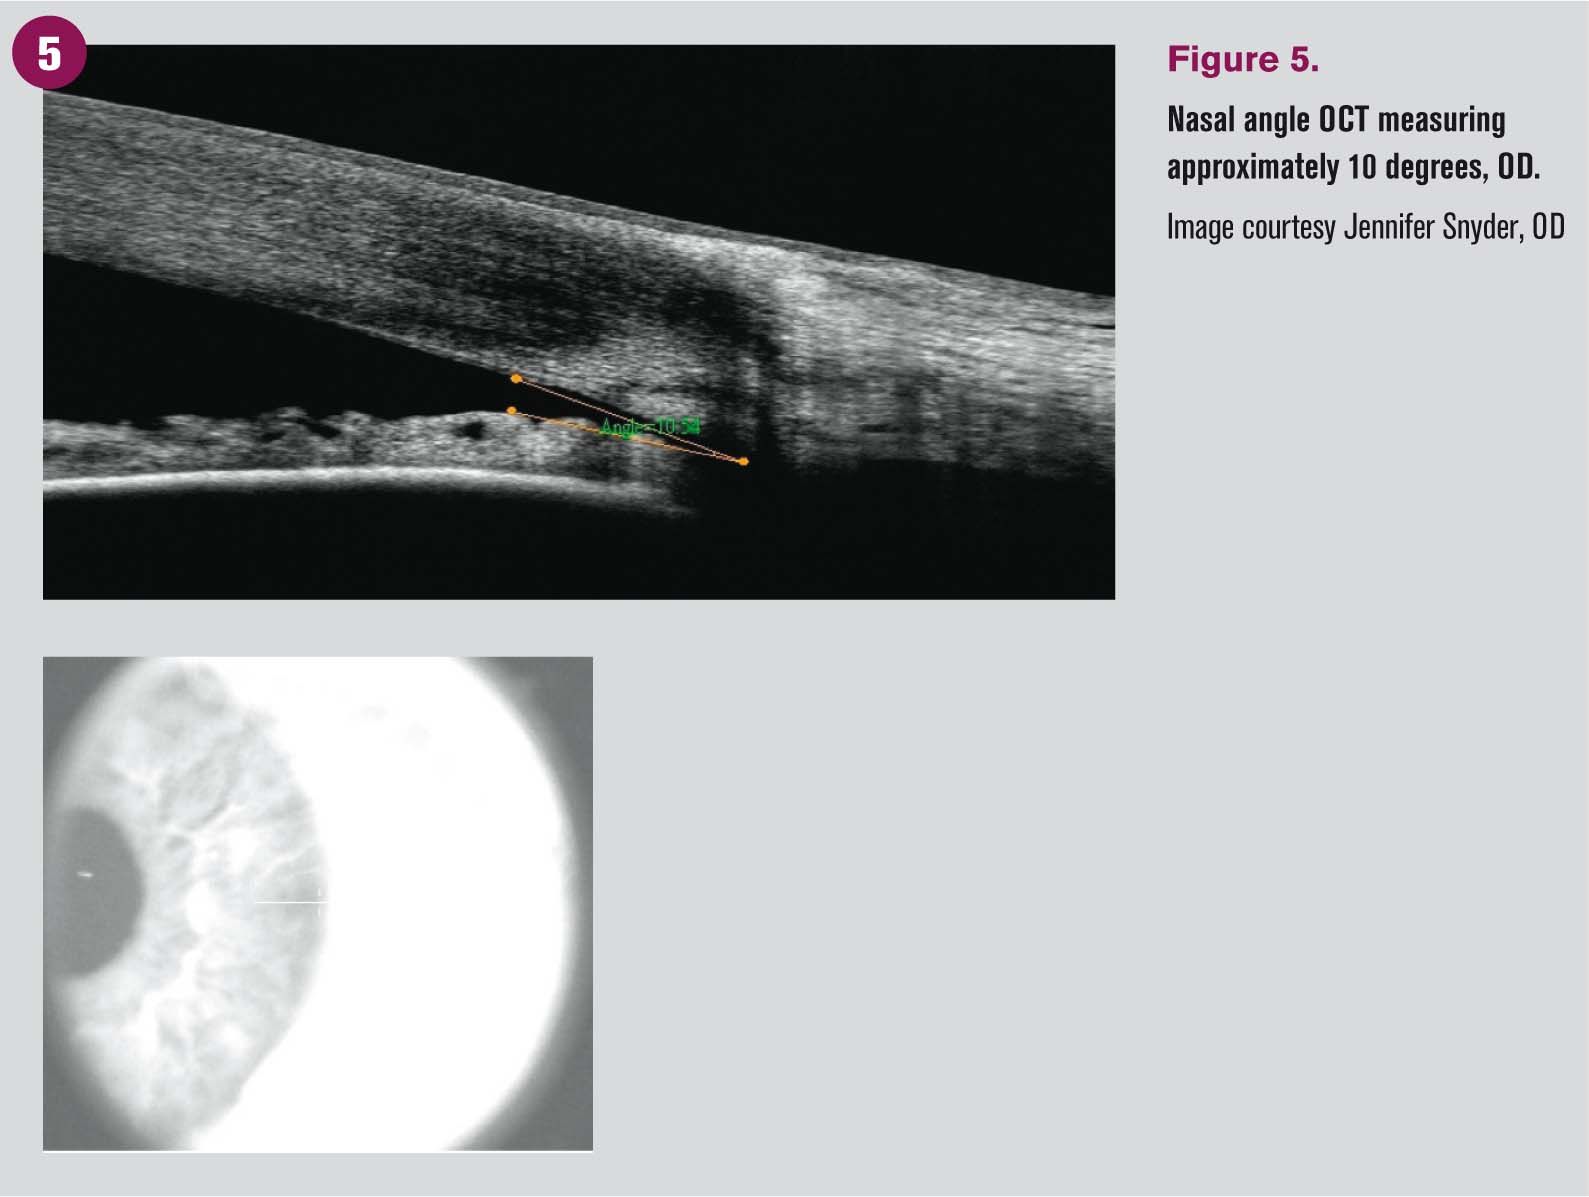

Gonioscopy is the standard for visualizing and diagnosing angle closure. It is important to evaluate all angles carefully. If the most posterior structure visible is the posterior trabecular meshwork, the angle is described as narrow. If only the anterior trabecular meshwork is visible, the angle is typically open 10 degrees or less and is likely to close. If greater than 180 degrees of the angle is found to be narrow, that patient is considered to be at risk for angle closure.

Angle OCT and ultrasound biomicroscopy are useful adjunct imaging tools but may not reveal important characteristics such as peripheral anterior synechiae and should not replace gonioscopic evaluation. Note that these adjunct tests do not yield information about the amount of pigment in the trabecular meshwork.

Angle OCT imaging is also helpful in monitoring angle position status post treatment as well as for patient education.